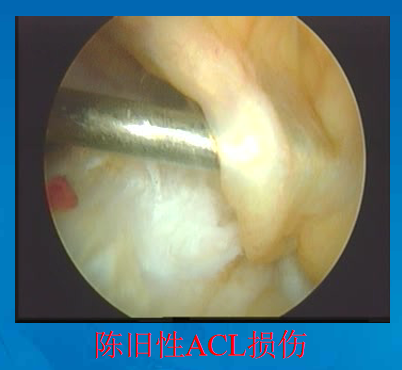

前交叉韧带损伤后形成的疤痕组织

关节镜下观

正常前交叉韧带

清理髁间窝

刨削切除ACL残端,以保证视野清晰以及准确定位